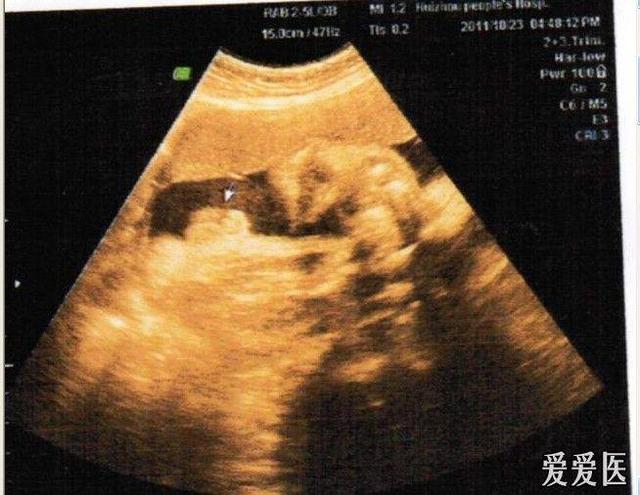

· 怀孕第17周,您可能会感觉到宝宝在您体内的运动,这种颤振称为“胎动”。

· 宝宝现在的身长约为 5 英寸(12.7 厘米),重约 5 盎司(将近 150 克)。